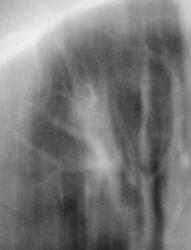

Иллюстрации 3, 4. Фрагменты изображения, полученного на CR – системе. Гомогенизация тени правого корня в области тела, измерены размеры «очагового образования» - 8 х 15 мм.